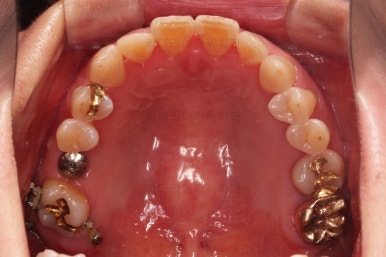

초진 때의 사진입니다.

전반적으로 치열이 삐뚤하고 불균일한 양상이긴 하지만 꼭 이런 부분들까지 교정해야 하는 건 아니에요.

제일 하단의 X-ray에서 문제점이 보이는데요.

해당 부분의 어금니 1개가 없었어요.

어금니가 없어진지 꽤 시간이 흘렀기 때문에 몇 가지 문제점이 나타나는데요.

치아가 없는 자리에 바로 임플란트가 불가능합니다.

치아를 뽑자마자 임플란트를 했다면, 치료는 간단했겠지만 이번의 경우는 시간이 오래 지나서 뒤쪽 어금니가 발치된 자리로 쓰러졌어요.

앞쪽 치열들도 발치된 자리로 조금씩 이동하는 바람에 틈새가 듬성듬성 생겼어요.